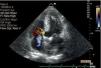

Três meses mais tarde, em reavaliação ecocardiográfica transtorácica, para além da ausência de vegetações valvulares, havia a referir melhoria na regurgitação tricúspide, que passou de moderada a ligeira e a PSAP era de 55mmHg. Verificou-se ainda a existência de fluxo turbulento de alta velocidade (6 m/s) ao nível do septo interventricular (SIV) alto, compatível com comunicação interventricular (Figura 7). Efetuou ecocardiograma transesofágico, que confirmou a presença de CIV perimembranosa restritiva de pequenas dimensões com shunt de predomínio esquerdo-direito (Figura 7), hipertrofia ventricular esquerda [septo interventricular (SIV): 15mm, parede posterior (PP): 12mm], diâmetro telediastólico do VE (DTDVE): 46mm, diâmetro telessistólico do VE (DTSVE): 29mm; massa ventricular esquerda (MVE=245 g) e hipertensão pulmonar moderada (PSAP: 55mmHg).